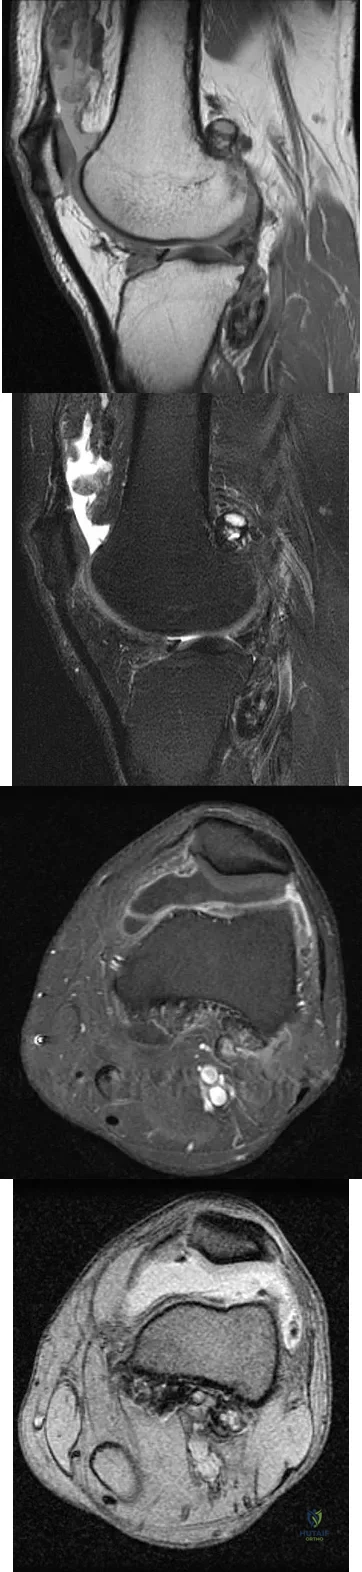

A 28-year-old man reports knee stiffness, swelling, and a constant ache that is worse with activity. Examination reveals an effusion, global tenderness, and warmth to the touch. Flexion is limited to 110 degrees. Figures 48a through 48d show sagittal T1-weighted, sagittal T2-weighted, axial T1-weighted fat-saturated gadolinium, and axial gradient echo MRI scans. Based on these findings, what is the most likely diagnosis?

Explanation